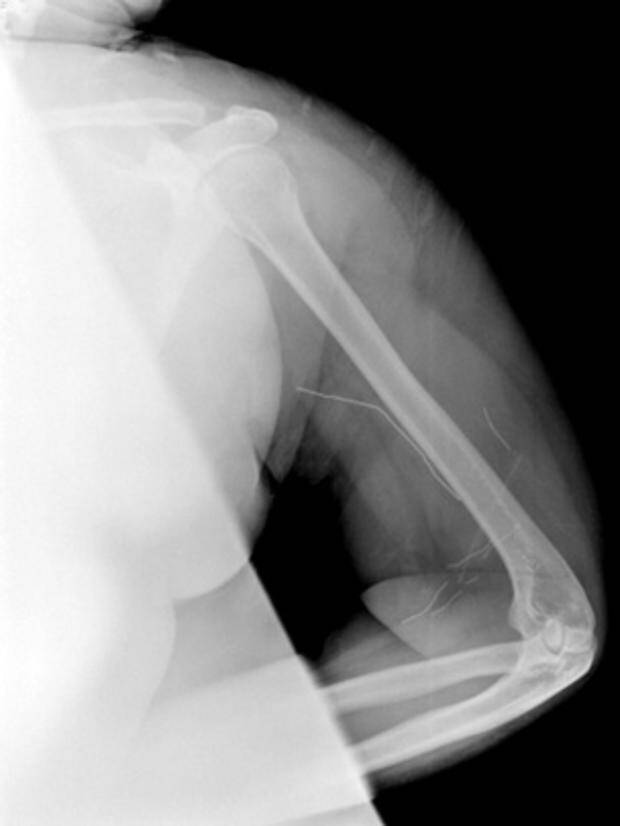

Niektórym osobom, zwłaszcza w wieku nastoletnim, trudno jest się powstrzymać od umieszczania rzeczy pod swoją skórą. Lekarze twierdzą, że rośnie liczba nastolatków – zwłaszcza z depresją lub lękami – które wbijają igły, zszywki, spinacze oraz inne przedmioty pod skórę swojego ciała. Tę dość bezkrwawą praktykę lekarze nazywają czasem “zachowaniem samo-osadzającym” lub “zagnieżdżającym”.

Samookaleczenia są niebezpieczne – oprócz ryzyka wywołania infekcji, umieszczanie w ciele przedmiotów może uszkodzić nerwy lub naczynia krwionośne. – W skrajnych przypadkach oprócz krwawienia (w tym wewnętrznego) może wystąpić nawet udar – powiedział Shiels.

– Jeśli dasz niektórym z tych dzieciaków magazyn do poczytania, to odzyskasz go z brakującymi zszywkami – mówi Shils. – Daj im ołówek, a wyciągną grafit i wsadzą do pod skórę.

Osoby, które dokonują takich czynów zazwyczaj dobrze reagują na psychoterapię lub/i terapię lękową. Jednakże najpierw trzeba zauważyć i obserwować to zachowanie. Shiels twierdzi, że rodzice oraz nauczyciele powinni rozważyć, czy to zachowanie nie występuje u nastolatków, którzy mają niewyjaśnione bóle lub infekcje skóry, a także u tych, którzy próbują ukrywać ręce, nogi czy nadgarstki – zwłaszcza kiedy podczas upałów zakładają długie spodnie czy bluzy z długimi rękawami.